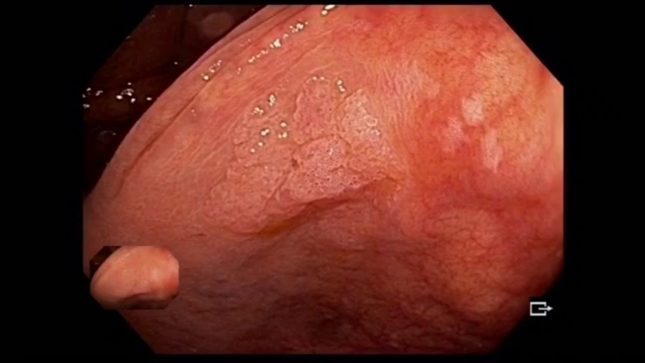

serrated polyposis syndrome – SPS היא תסמונת היפרפלסטית של רקמת המעי עם פרדיספוזיציה משמעותית להתפתחות ממארת של סרטן המעי הגס (CRC).

זוהי תסמונת יחסית חדשה שאיננה מוכרת דיה. מחקרים קודמים דיווחו ששיעורי ההחמצה של אבחנת ה- SPS משתנים מ-40% ל-82%. מאחר שחולי SPS וקרובי משפחתם מדרגה ראשונה הם בעלי סיכון מוגבר משמעותית לCRC, זיהוי מוקדם הוא חשוב. קבוצת גסטרואנטרולוגים מהולנד בצעו מחקר בניסיון לקבוע את שיעור הפספוס של SPS ולקבוע את הסיבות להחמצת אבחונים.